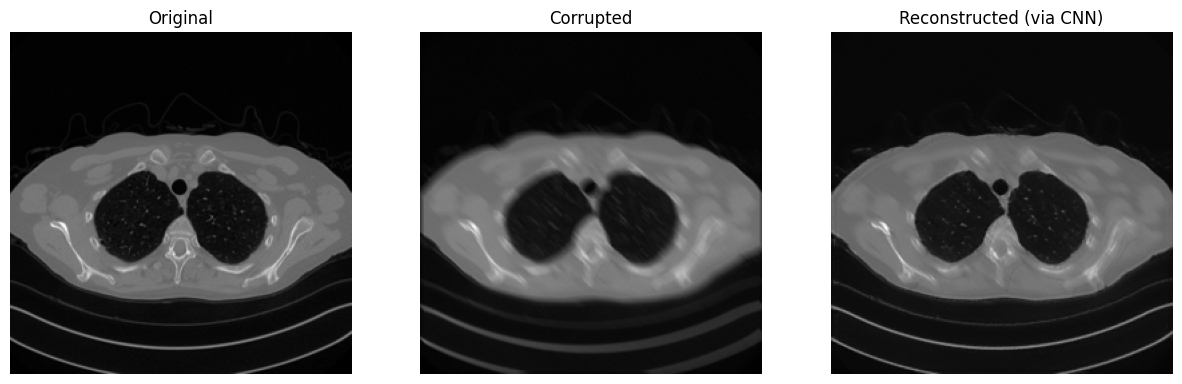

# Visualize

plt.figure(figsize=(15, 5))

plt.subplot(1, 3, 1)

plt.imshow(x_true.detach().cpu().squeeze(), cmap='gray')

plt.axis('off')

plt.title('Original')

plt.subplot(1, 3, 2)

plt.imshow(y_delta.detach().cpu().squeeze(), cmap='gray')

plt.title('Corrupted')

plt.subplot(1, 3, 3)

plt.imshow(x_rec.detach().cpu().squeeze(), cmap='gray')

plt.title('Reconstructed (via CNN)')

plt.show()

Shape of x_true: torch.Size([1, 1, 256, 256]). Range of x_true: (tensor(0.), tensor(0.9348))

SSIM: 0.9409